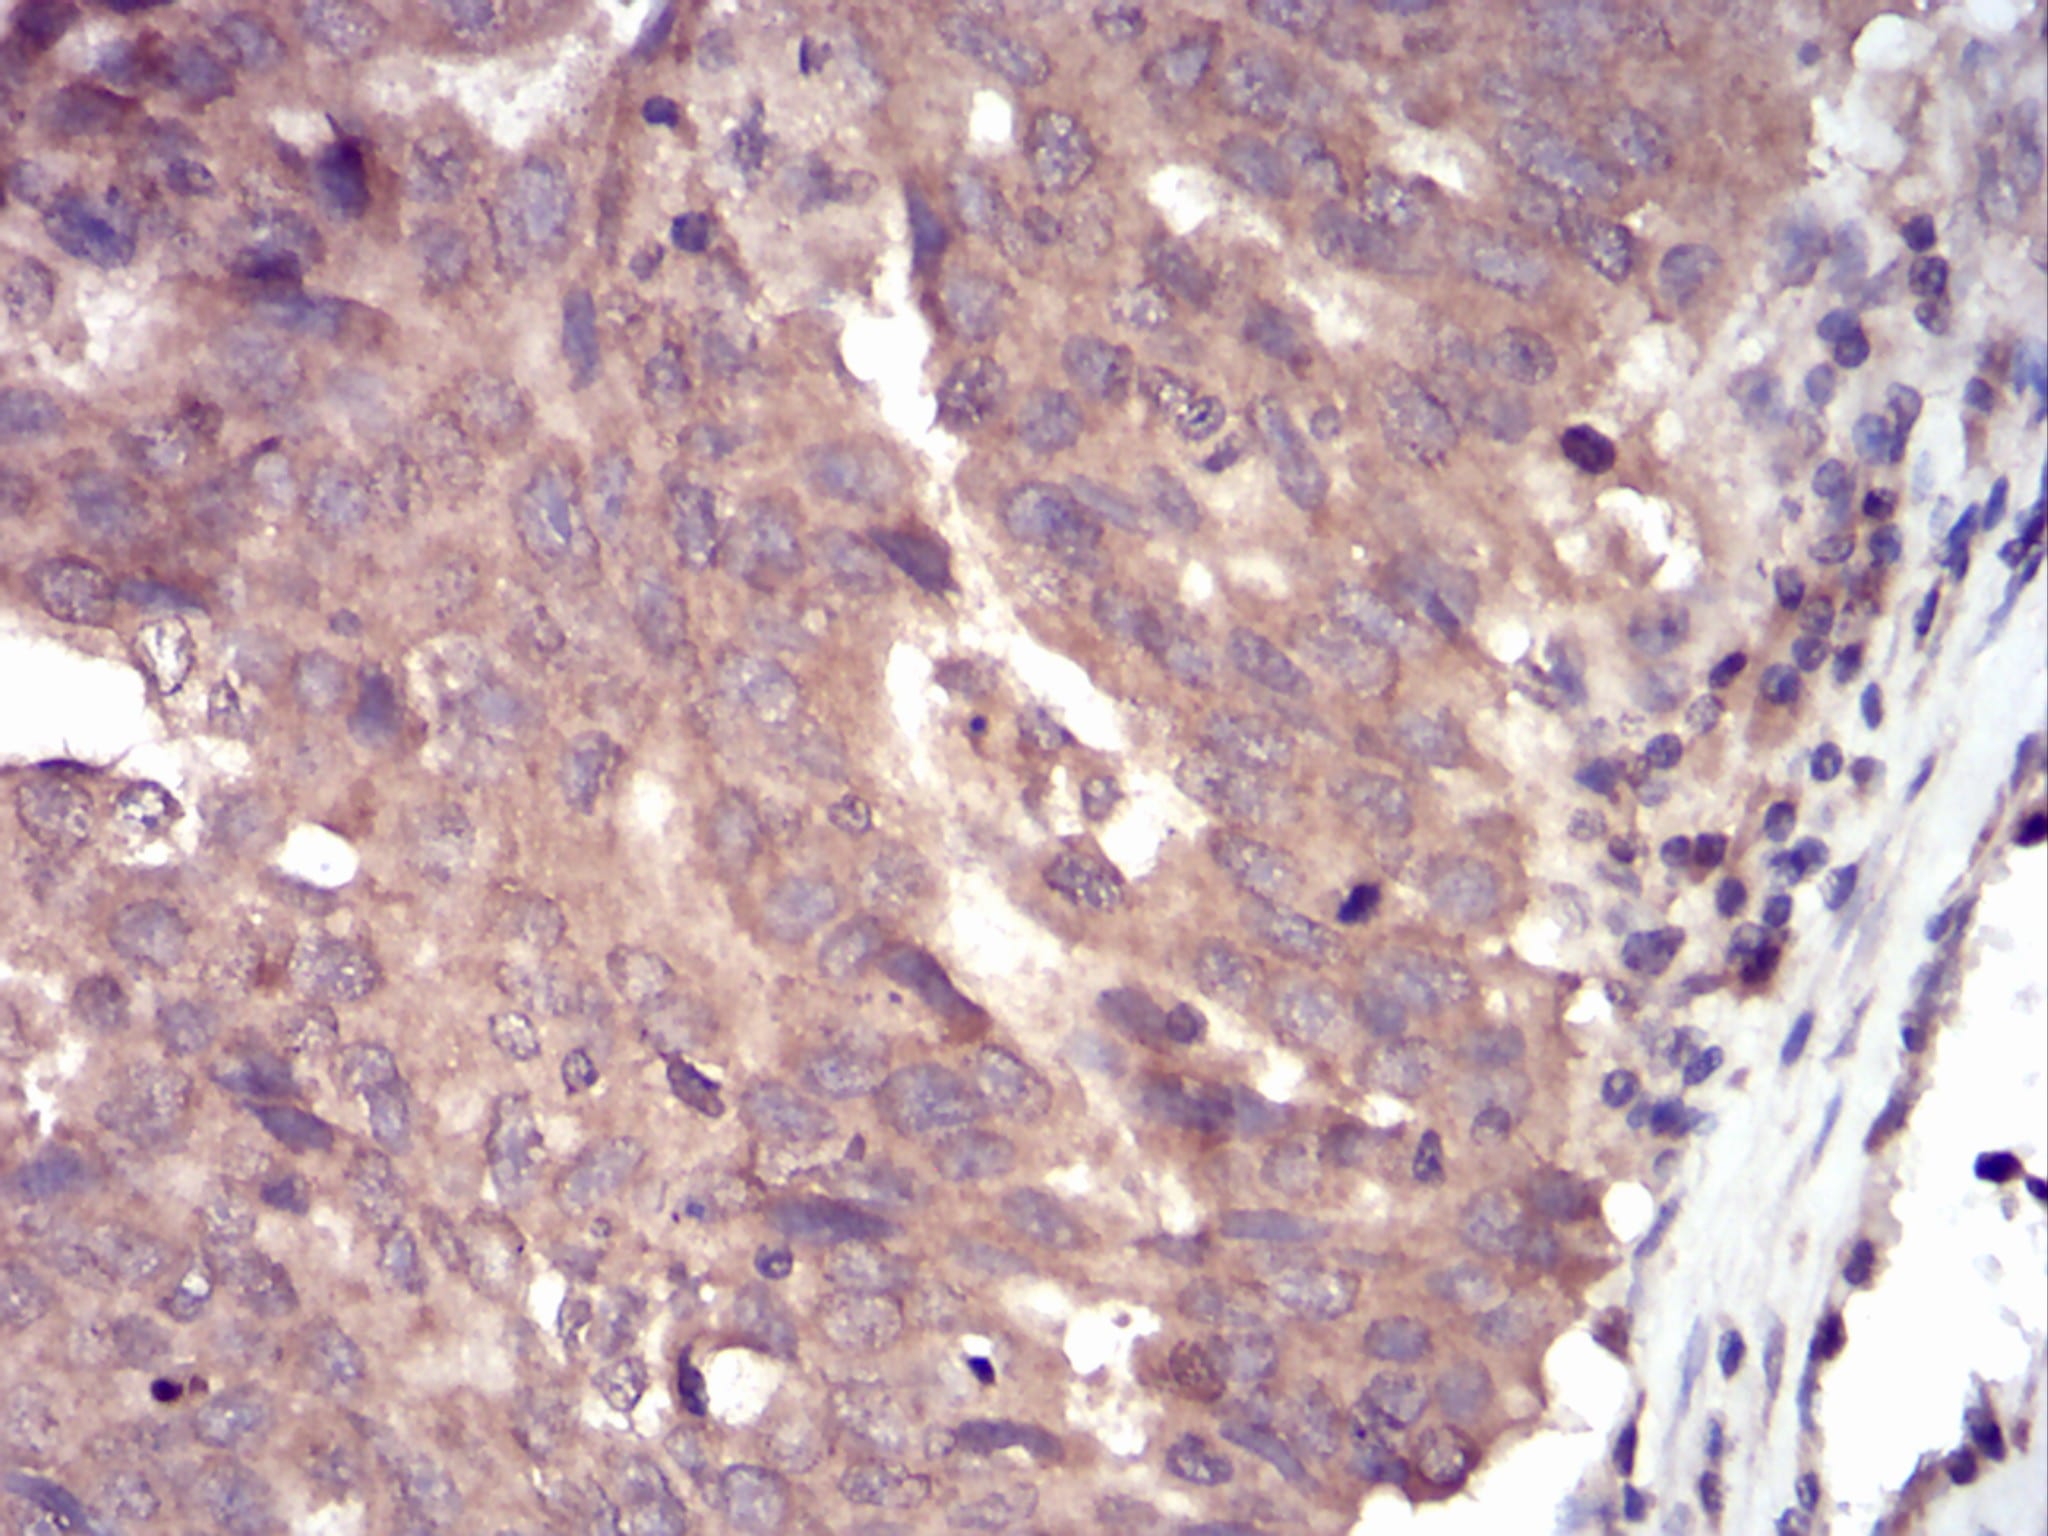

分类: 科研抗体货号: 30742别名: SSH1;SSH1L应用: IHC,FCM反应种属: Human